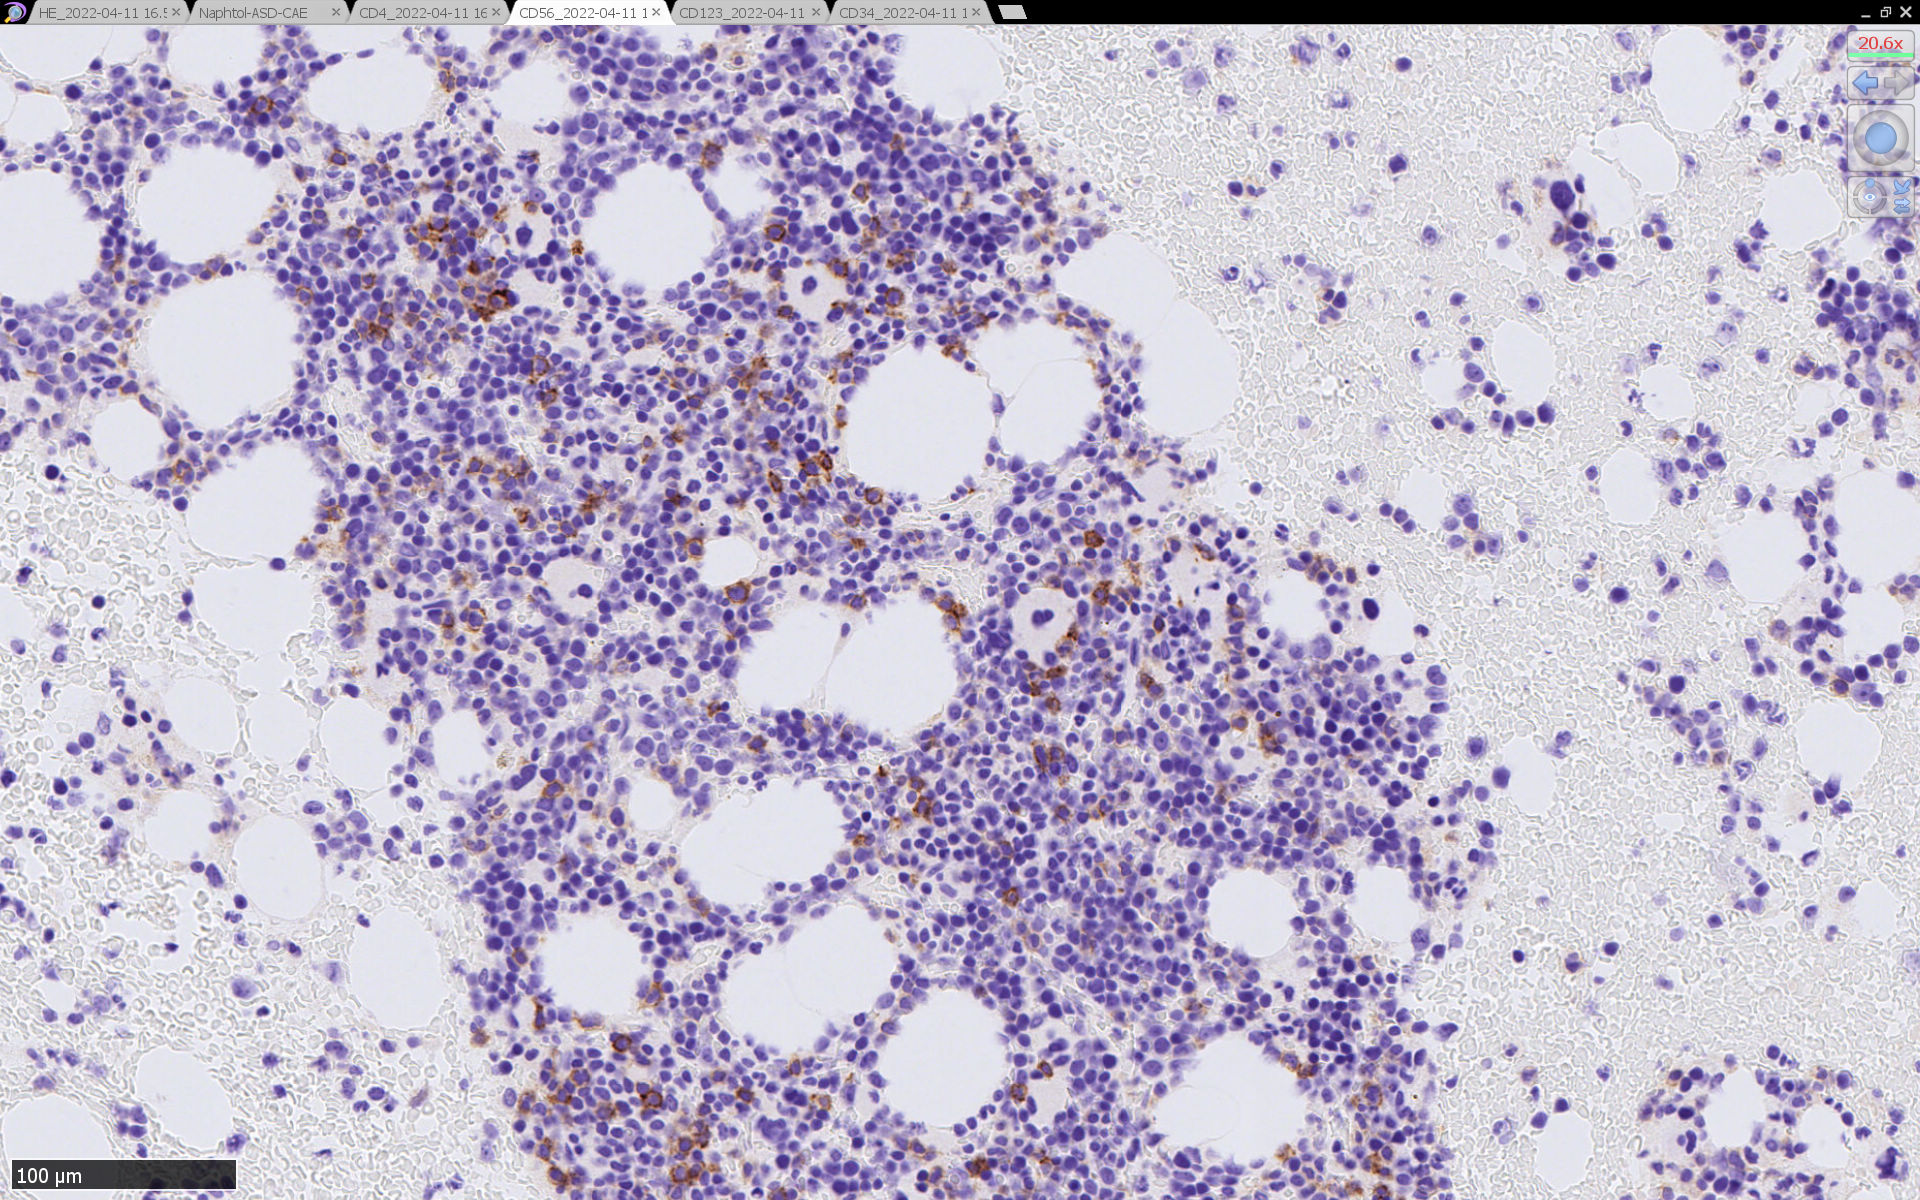

HEでは腫瘍細胞の同定が難しい. 本症例は ASD-Giemsa染色を見ても, 腫瘍胞巣はよくわからなかった. 皮膚が先に診断がつき, 次いでBone marrowだったため, 免疫染色にすすめたが, Bone marrowが先だと診断に困ったかもしれない.

免疫染色

CD4は染まりすぎの感がある(濃く染まる細胞はCD4+ T-cellかもしれない). CD56, CD123が陽性で可能性が高くなり, BPDCNの診断にはCD34は陰性であることが必要

TCF4、CD123、TCL1をconsultationにより染色していただき, 陽性を確認した. CD34-, lysozyme-, CD123(おいてある病院は少ないかも)をしらべて, BPDCN研究会あてconsultationをする流れでしょうか.